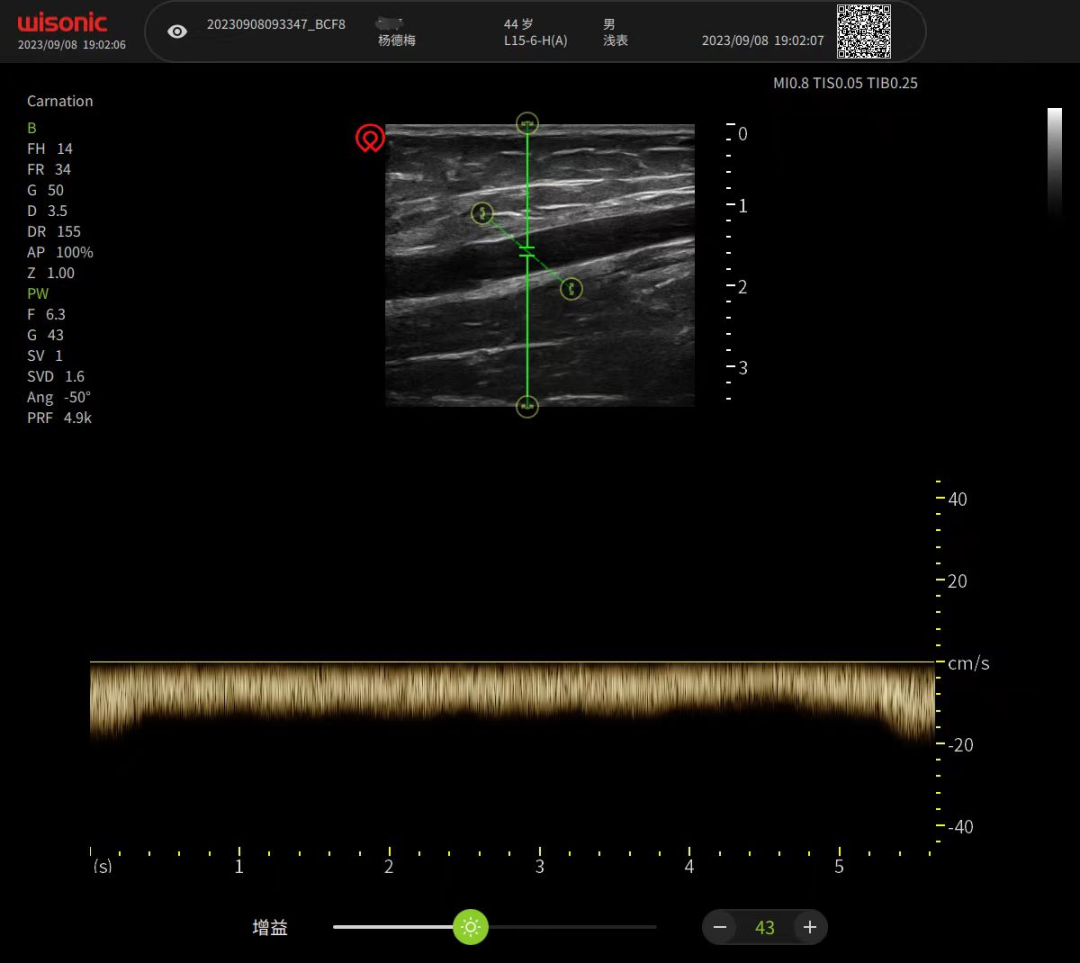

动静脉穿刺置管

超声引导下动静脉置管穿刺可动态观察患者血管,有利于定位穿刺和引导穿刺。部分患者由于长期输液、肥胖、水肿等原因,导致外周静脉条件较差,血管穿刺困难,此时选用超声引导进行血管评估、穿刺,可快速有效建立静脉通路,让护士成为扎针“神枪手”。